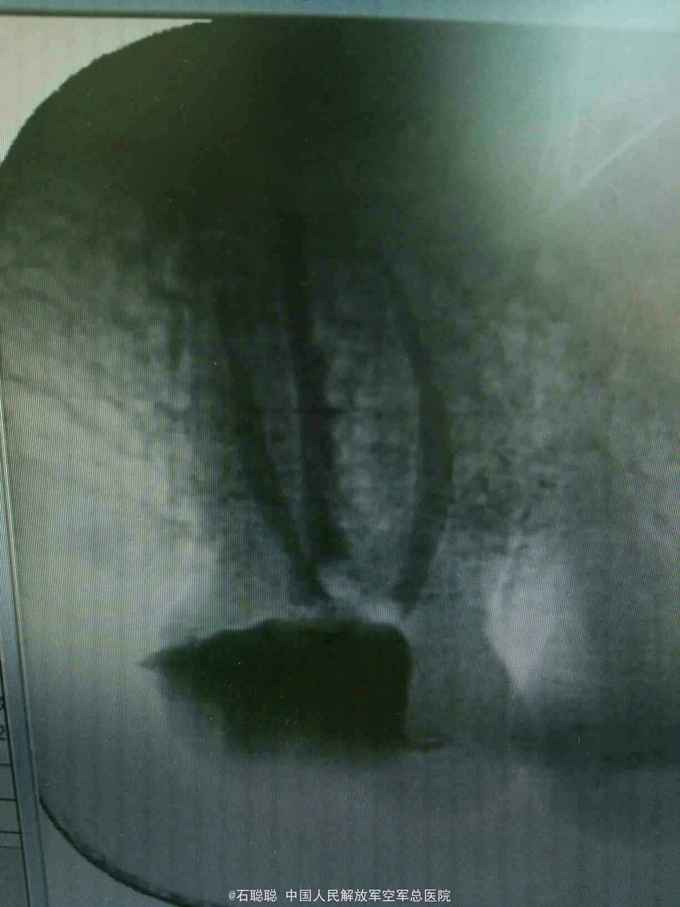

诊断:右上7慢性牙髓炎急性发作 治疗计划:右上7RCT后冠修复 处置:右上7碧蓝局麻下开髓,去腐,揭顶,探及近颊、远颊、腭侧三个根管口,略疏通,见血性渗出,冲洗,干燥,置失活剂,氧化锌暂封 一周后复诊:诉无不适 查:右上7氧化锌完整在位,叩痛-,不松动,牙龈未见异常 处置:右上7去除氧化锌暂封,测工作长度,近颊=远颊=19mm,扩大至30#,腭根=21mm,扩大至35#,冲洗,干燥,置CP棉球,氧化锌暂封 一周后复诊:诉无不适 查:右上7氧化锌完整在位,叩痛-,不松动,牙龈未见异常 处置:右上7去除氧化锌暂封,试主尖,冲洗、干燥,冷侧压充填,置干棉球,氧化锌暂封 嘱:勿用患牙咀嚼 一周后择期修复